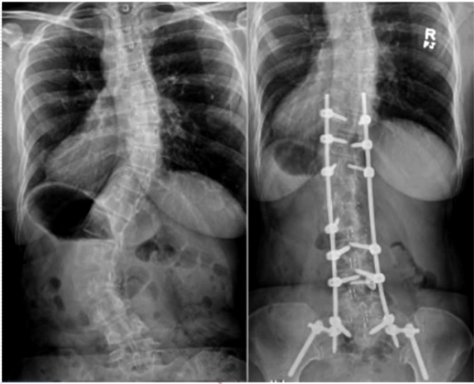

減少退變(bian)性(xing)側彎的(de)置釘數量(liang)

對于退(tui)變性側彎/后凸畸形患者(zhe),可以選(xuan)擇一(yi)期融合+二期固定的方式,可以降低置釘數量(liang),減少對相關(guan)節段骨(gu)性結構及軟組織(zhi)的損傷。